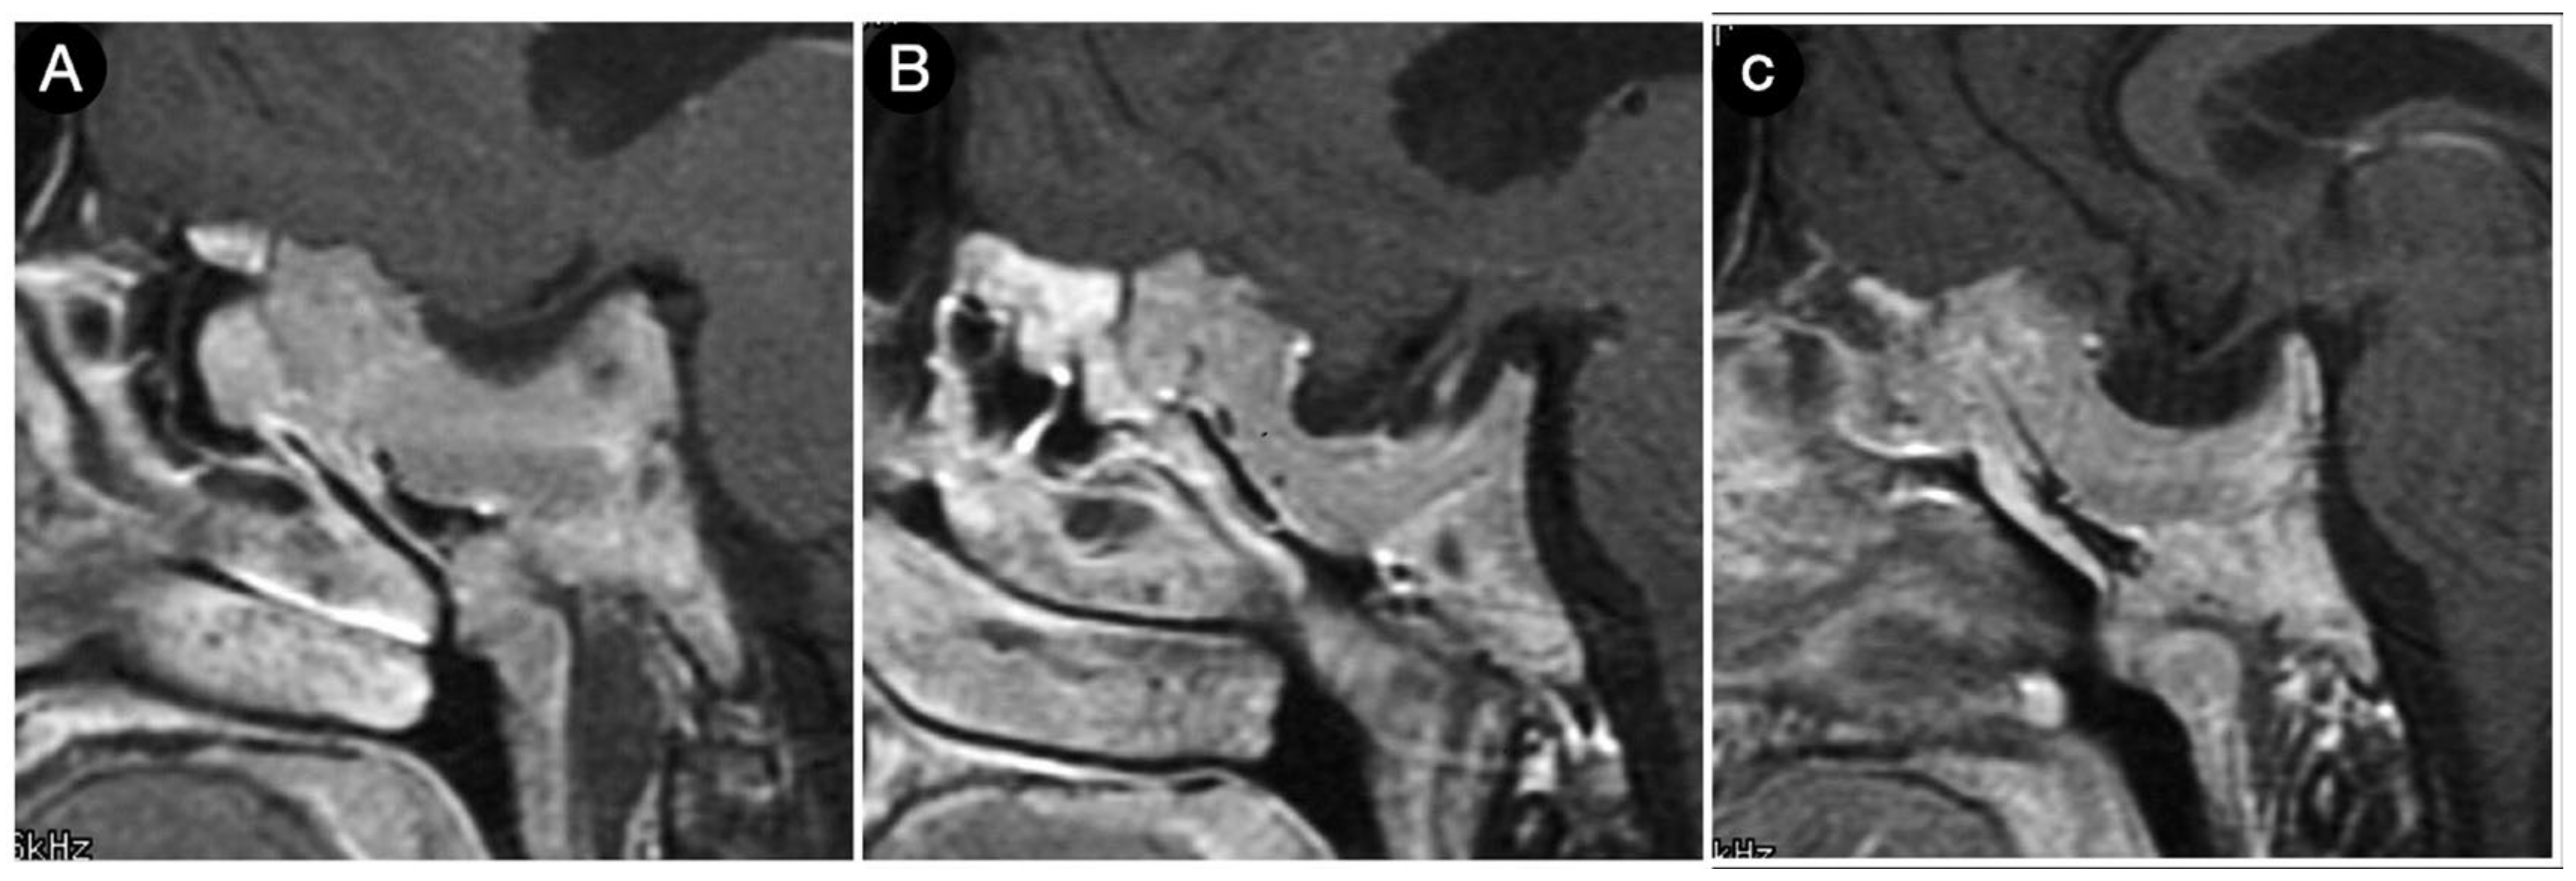

Case #1: Infradiaphragmantic Tumor with Middle Fossa Involvement through the Cavernous Sinus